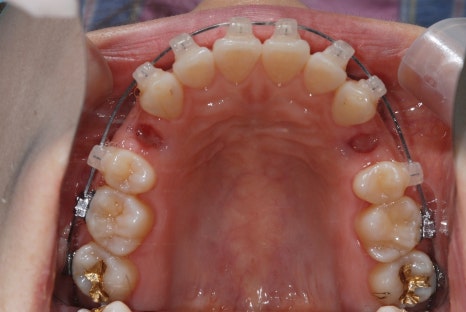

<Before-and-after orthodontic treatment photos>

Treatment period: 23.05.15 - 24.10.21 (about 1 year and 6 months)

Treatment performed: crowded teeth, alignment improvement

Treatment period: 23.01.18 - 24.6.04 (about 1 year and 6 months)

Treatment performed: protrusion, midline improvement

*The before-and-after photos were posted with the patient's consent and were taken in the same environment and under the same conditions.